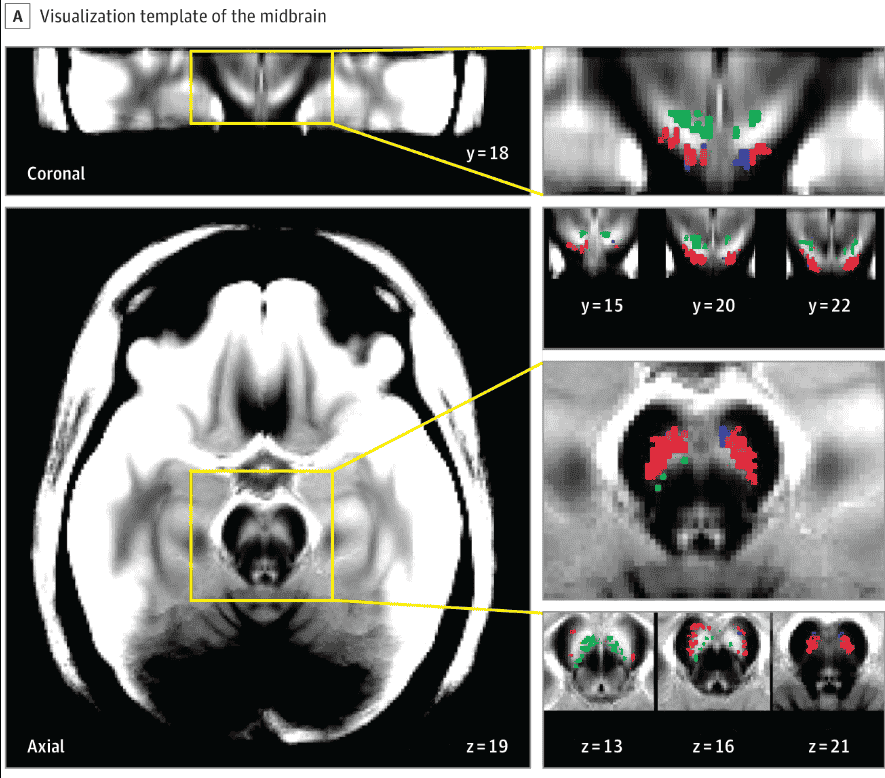

Penelitian dari McGill University di Kanada menemukan penyebab psikosis pada pengguna ganja diakibatkan oleh hormon dopamin, bukan karena senyawa cannabinoid THC. Hasil visual mesin MRI (Magnetic Resonance Imaging) mendeteksi adanya peningkatan sinyal neuromelanin di bagian otak tengah yang mengidentifikasikan keberadaan hormon dopamin. Fungsi dopamin adalah sebagai neurotransmitter; penghantar pesan atau sinyal antar sel saraf (neuron) di otak dan tubuh yang mengatur suasana hati (mood) dan mempengaruhi motivasi seseorang. Kelebihan hormon dopamin menyebabkan kesenangan atau kenikmatan berlebih yang dikaitkkan dengan psikosis.

Riset dilakukan dengan metode penelitian kohort longitudinal yang melibatkan 61 orang pengguna ganja selama satu tahun, termasuk individu yang teridentifikasi memiliki gejala psikosis awal. Peneliti mengamati adanya peningkatan sinyal hormon dopamin pada kelompok dengan gejala psikosis awal, dan tidak menunjukkan peningkatan dopamin dalam kelompok tanpa gejala psikosis awal selama penelitian berlangsung.